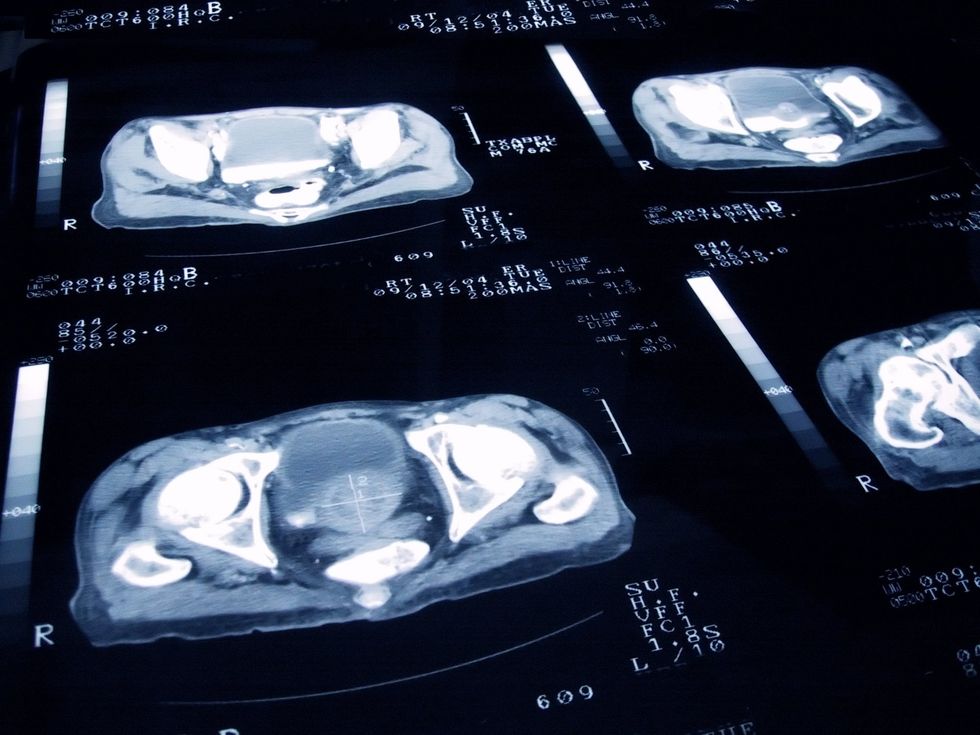

Researchers are testing whether combining PSA blood tests with rapid MRI scans might prove effective enough to justify screening all men. Results are expected within two years.